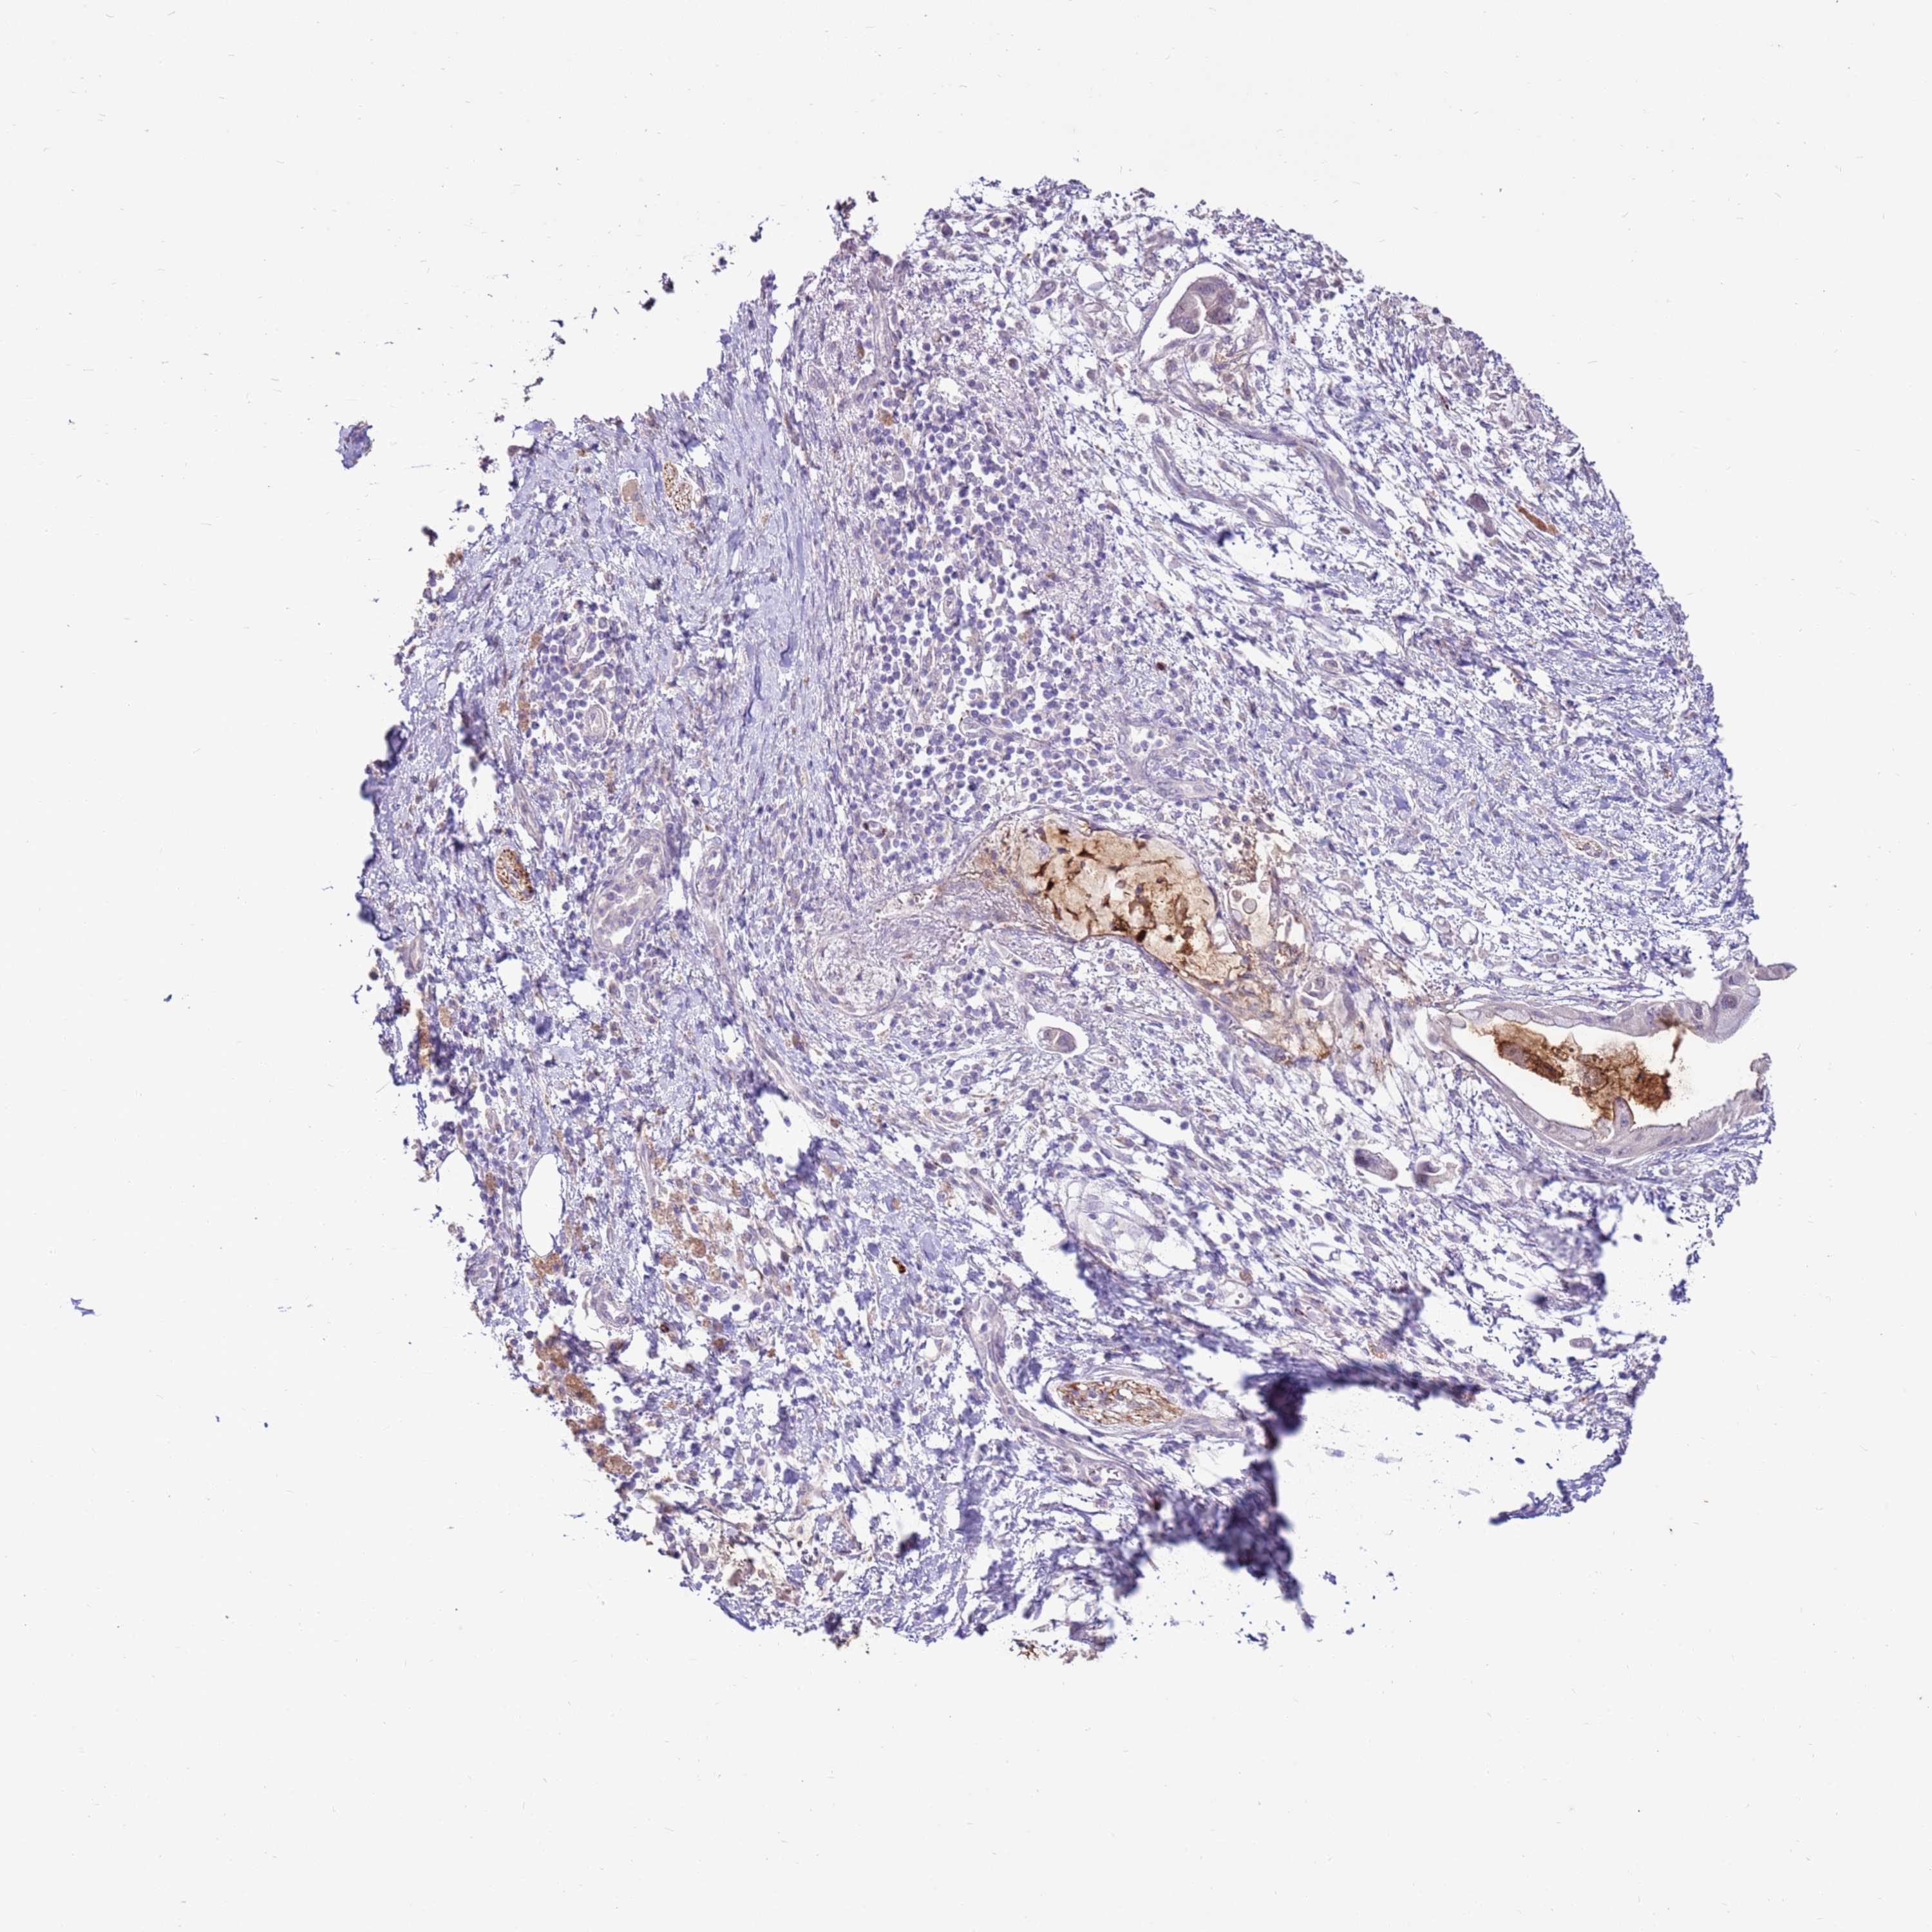

PANCREATIC CANCER - Protein expressioni

A mouse-over function shows sample information and annotation data. Click on an image to view it in a full screen mode. Samples can be filtered based on level of antibody staining by selecting one or several of the following categories: high, medium, low and not detected. The assay and annotation is described here.

Note that samples used for immunohistochemistry by the Human Protein Atlas do not correspond to samples in the TCGA dataset.

Antibody stainingi

Antibody staining in the annotated cell types in the current human tissue is reported as not detected, low, medium, or high, based on conventional immunohistochemistry profiling in selected tissues. This score is based on the combination of the staining intensity and fraction of stained cells.

Each image is clickable and will lead to virtual microscopy that enables deeper exploration of all samples and also displays staining intensity scores, fraction scores and subcellular localization as well as patient and tissue information for each sample.

Antibody HPA042116

Antibody HPA043556

Staining

High

Medium

Low

Not detected

Intensity

Strong

Moderate

Weak

Negative

Quantity

>75%

75%-25%

<25%

None

Location

Nuclear

Cytoplasmic/membranous

Cytoplasmic/membranous,nuclear

Adenocarcinoma, NOS